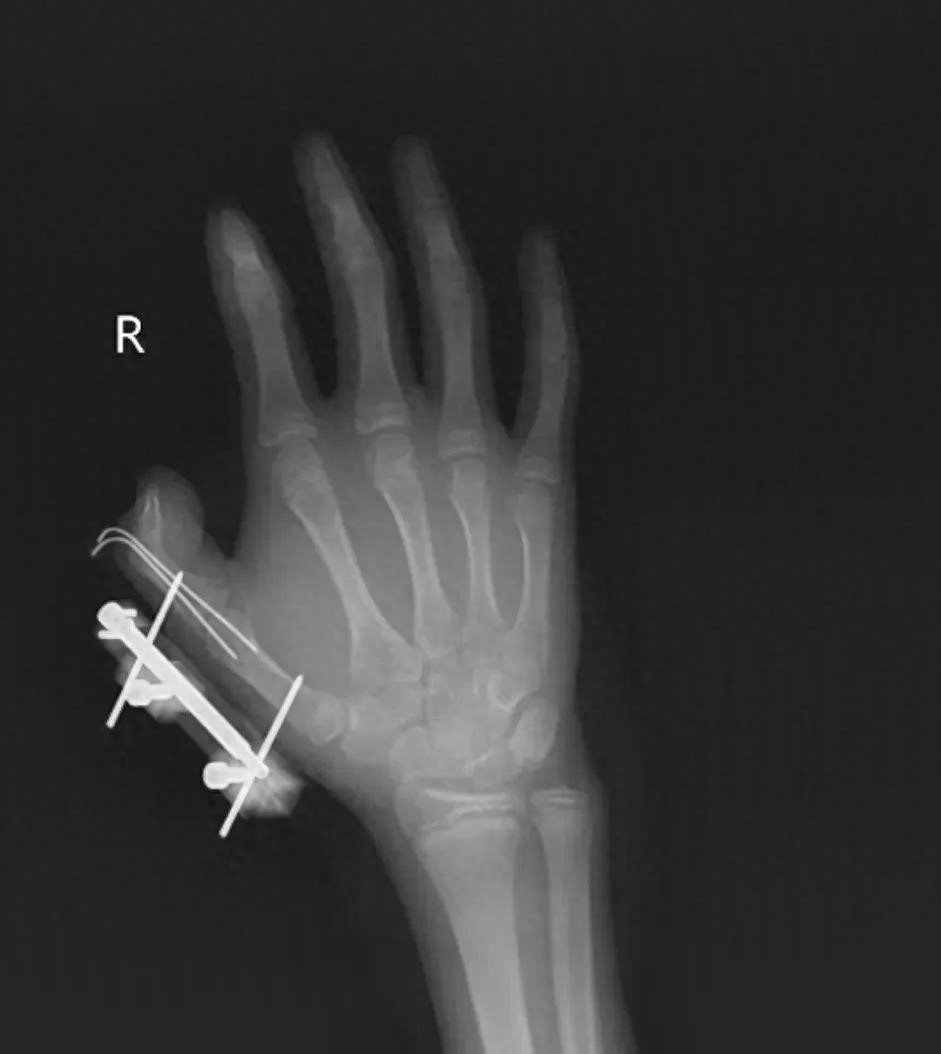

14岁少年手指被炸伤

突然,密封袋里的干冰发生爆炸,维维的右手瞬间鲜血直流,拇指虎口处被撕开一道约10厘米的伤口,肌肉组织断裂外露,还伴随拇指骨折、关节脱位,整个拇指完全失去知觉。

经治疗,维维的拇指保住了,但后续还需长期康复训练,才能慢慢恢复手部精细动作功能。